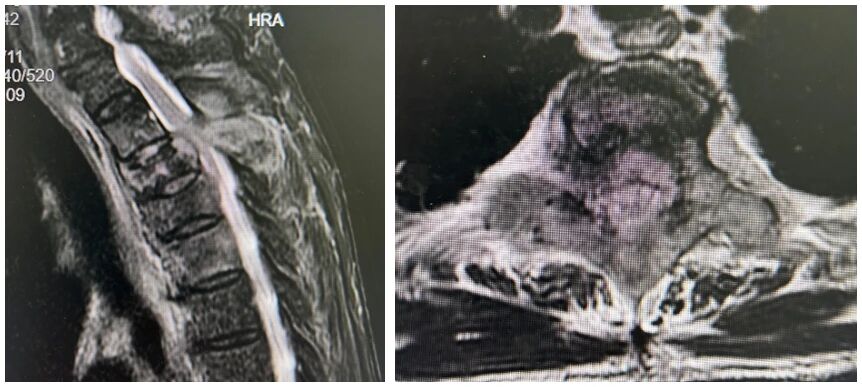

近期,他因双下肢麻木、乏力再次入益阳市中心医院治疗。完善相关检查后诊断为脊柱转移瘤、双下肢不全瘫(Frankle分级 C级),肿瘤细胞转移至上胸椎,胸3-4层面脊髓受压,导致患者双下肢肌力评级仅为1-2级,乳头以下平面感觉丢失。

(磁共振显示胸3、胸4椎体骨质破坏,相应层面脊髓受压变性)

(磁共振显示胸椎椎体骨质破坏)